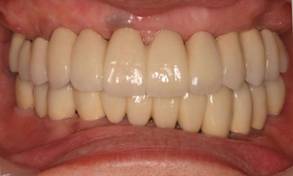

術後。上部構造はハイブリッドレジンです。しっかり嚙めるようになり喜んでいただきました。

上部構造装着後6年。ハイブリッドレジンを使用したため、少し艶がなくなってきました。上部構造の材料には金属、ハイブリッドレジン、セラミックなどがあります。セラミックはきれいですが欠けやすいため、最近はフルジルコニアを使っています。

上顎 少しすり減ってきました。

下顎。12か月に一度メインテナンスをしています。

インプラント装着後6年。順調に経過しています。12か月毎のメインテナンスをしています。